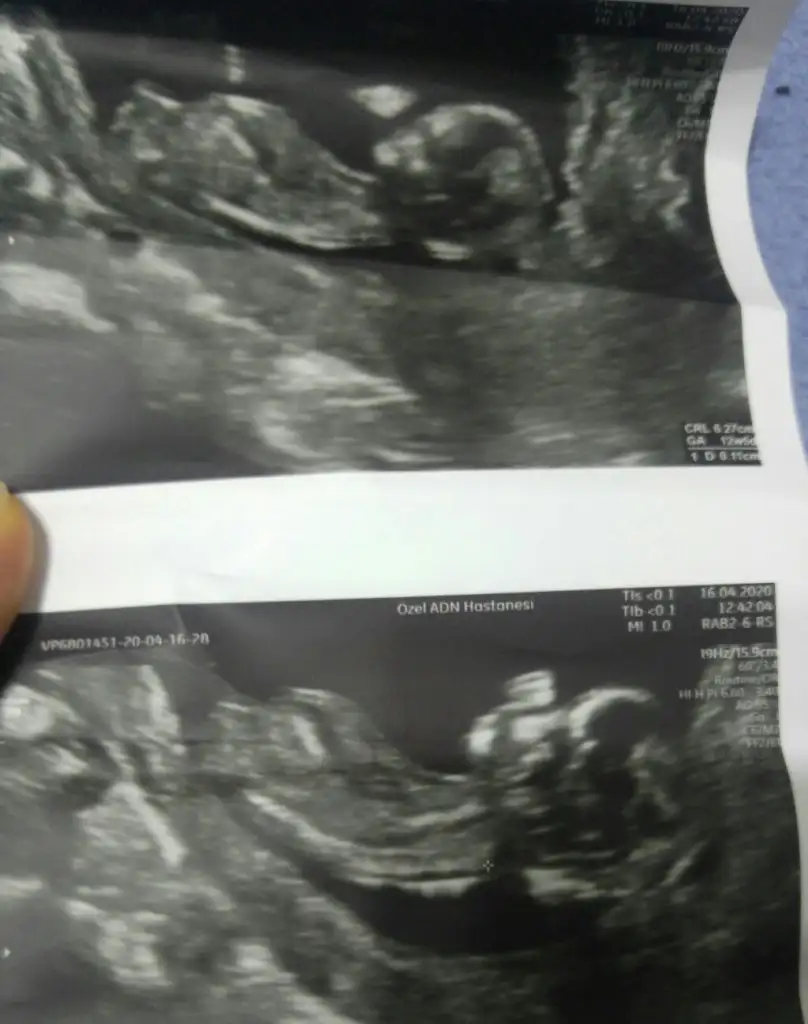

8 hafta ya göre erkek ama siz 11 12 13 hafta nub için paylaşınbize de tahmin yaparmısınız. ikisi de karından usg. ilk resim 9+4 ikincisi 8

Bundan sonra gidemeyecgm sanirim cinsiyet vakti 14 15 .haftalar giderim nasil anladiniz kiz acabaBuna göre kızama siz 11 12 13 hafta nub için paylaşın

Çok tesekkur ederim zahmet olmasa buna da bakabilir misiniz kardesimin 8 haftalikBuna göre kızama siz 11 12 13 hafta nub için paylaşın